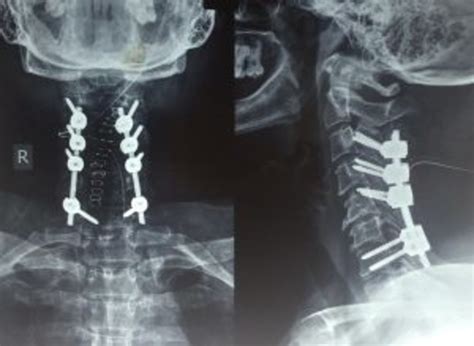

The fusion component involves connecting two or more vertebrae permanently. Using bone grafts, metal rods, and screws, the surgeon facilitates a biological process where the bones grow together into a single, solid unit. This prevents painful movement between the vertebrae and provides the support necessary to prevent future spinal instability.

The Surgical Experience and Recovery

• laminectomy with fusion and fixation